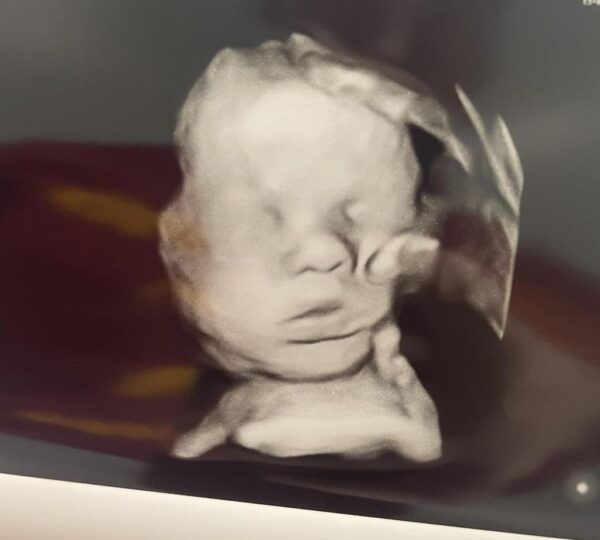

By June 20, Amanda shared another update, announcing that Kyler, at 36 weeks, had grown to over seven pounds, making him her largest baby to date and a healthy, thriving newborn despite earlier medical concerns.

She wrote, “Our chunky boy is going to be the biggest baby I’ve officially ever had. Today they monitored his practice breathing, and his measurements are ahead of schedule, which is exciting news.”

During that appointment, medical staff recorded Kyler’s heart rate at 132 beats per minute, confirming stable cardiac function. Amanda described his face as “sweet” and shared her excitement to finally hold him in her arms.